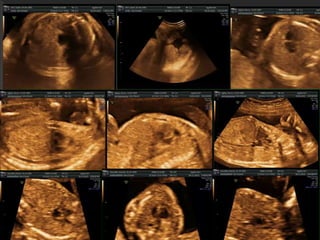

 Dört temelintrakardiyak görüntü: • Dört odacık görüntüsü • LVOT görüntüsü • 3 damar görüntüsü (3V) • Aortik arkın tranvers kesiti 4 CV LVOT RVOT Mide ,aort, omurga 3 VT • Fetal abdomenin standart kesitinden başlayıp toraks girişine kadar sürekli bir tranvers tarama yapılır • 5 aksiyal kesit elde edlir • Bu kesitler ile rutin fetal kalp taraması için gerekli olan tüm bilgiler elde edilebilir

 Diyaframın hemenüzerinde toraksın tranvers kesiti ile elde edilir  Fetusun oryantasyonuna bağlı apikal, lateral ya da ters apikal görüntü alabilir  Tümü analiz yapmak için uygundur  Fetal omurga aşağıda olduğunda ideal olarak görüntülenir

 DO kesiti‘crux’ merkeze alınarak analiz edilmelidir  Crux alt hizasından kesit alınırsa koroner sinüs, üst hizasından alınırsa LVOT görüntülenir  İnce bilek hareketleri ile doğru dört odacık görüntüsü elde edene kadar transdüseri hareket ettirin  Toraks daire şeklindedir ve bir kosta tam olarak görülebilir, birden fazla kosta görülüyorsa kesit eğik demekdir